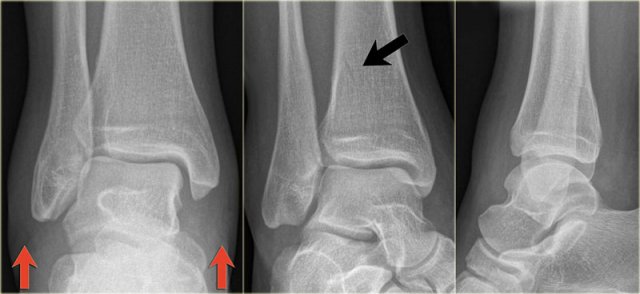

The images show an obvious Weber B fracture.

On the AP-view the linear lucency is the clue to a tertius fracture (red arrow).

It results from subtle malalignment of the fracture fragment.

Likewise in some cases malalignment can result in a linear density.

Trimalleolar Weber B fracture Trimalleolar Weber B fracture

In this case there is a Weber B fracture with avulsion of the medial malleolus.

The bright line on the AP-view indicates a large tertius fracture fragment.

This tertius fracture can also be seen on the lateral view, but in many cases we need all the information of both the lateral and AP-view to diagnose a tertius fracture.